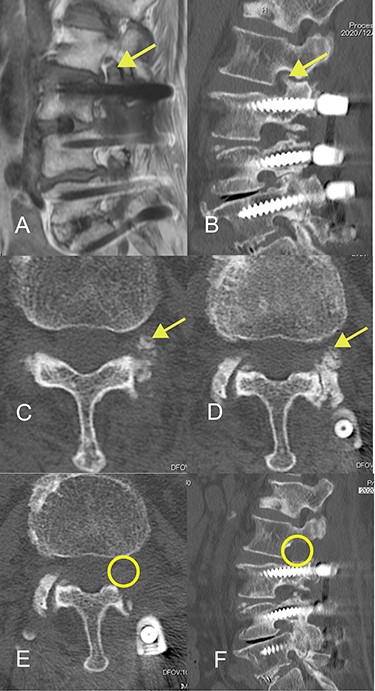

The patient was an 82-year-old Japanese woman who had presented 2 months earlier with pain and numbness in her left lower extremity. She had a history of vertebral fracture at L1 4 months previously for which she had been treated with a lumbar orthosis for 2 months (Fig. 1). Magnetic resonance imaging of the lumbar spine demonstrated foraminal stenosis at the L2–L3 level (Fig. 2A). CT images of the lumbar spine revealed ossification in the capsular portion of the ligamentum flavum around the L2–L3 facet joint (Fig. 2B–D). She underwent L2–L3 foraminotomy with excision of the capsular portion of the OLF. The patient’s symptoms disappeared immediately after surgery. Postoperative CT scans showed good decompression at the operated level (Fig. 2E and F).

Magnetic resonance and computed tomography (CT) images acquired at the time of onset of radiculopathy. (A) Sagittal T1-weighted magnetic resonance image showing moderate foraminal stenosis at the L2–L3 level. (B) Sagittal CT image showing ossification of the ligamentum flavum protruding into the foramen. (C, D) Axial CT image showing OLF in the capsular portion. (E, F) Postoperative CT image confirming adequate removal of the ossification of the ligamentum flavum.